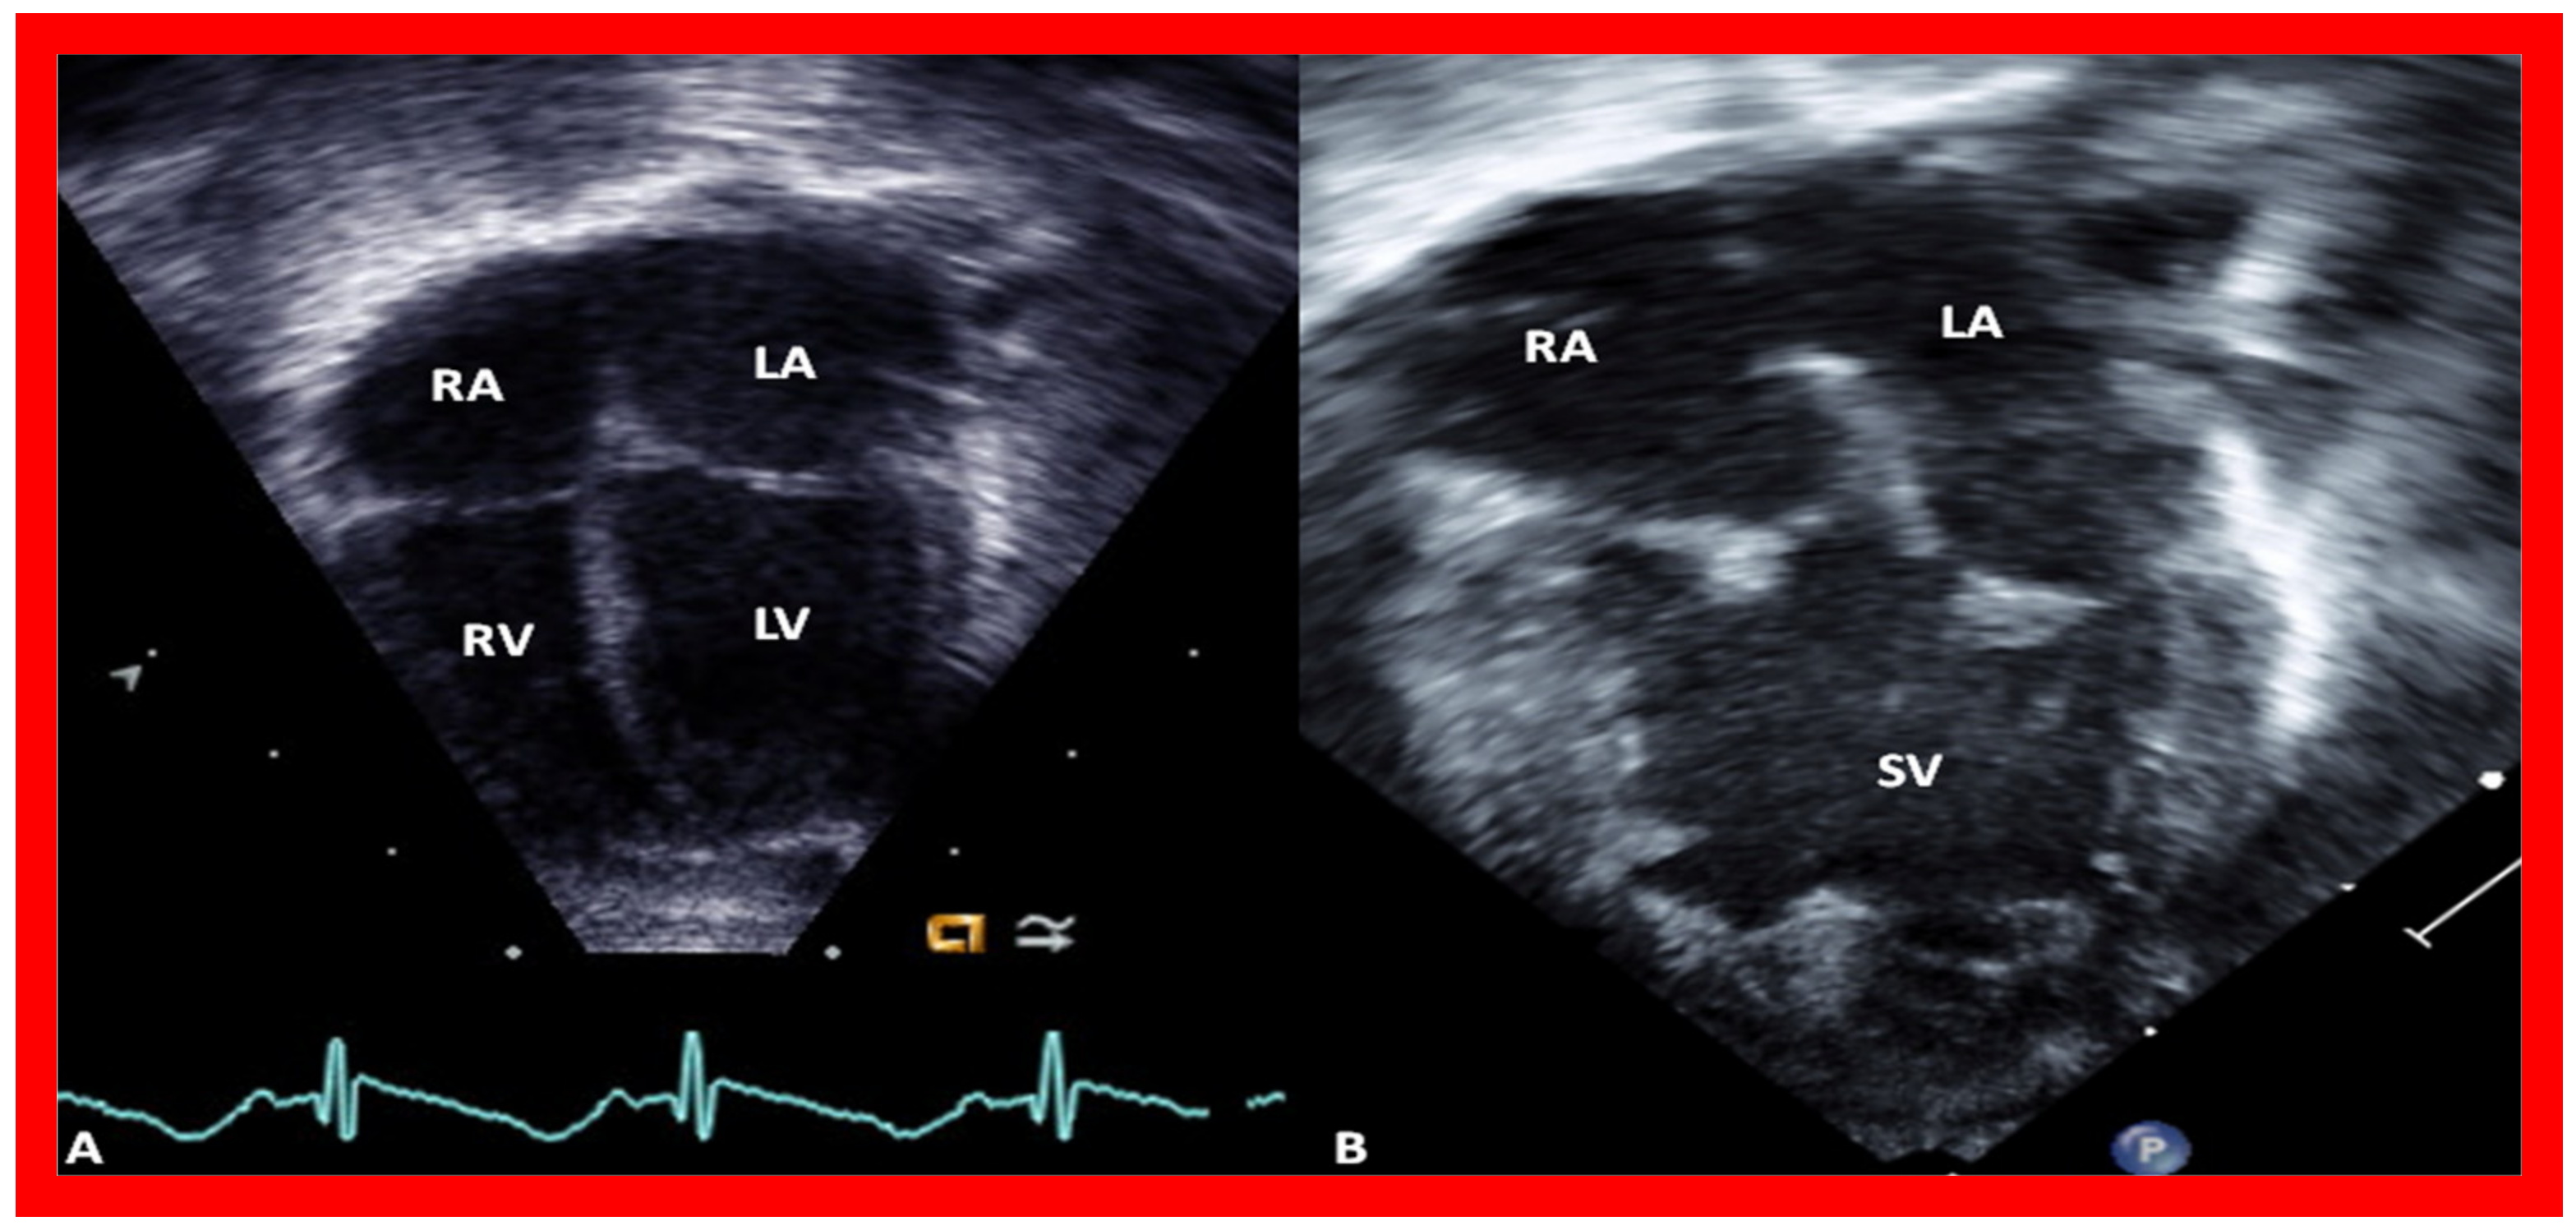

7. Echocardiogram